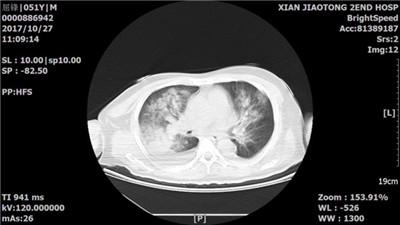

患者转入重症医学科后韩锋主治医师立即为患者实施气管插管并机械通气以纠正呼吸衰竭,予以多种血管活性药物以维持有效组织灌注,带着转运呼吸机复查CT等,明确了患者呼吸衰竭的原因是成人急性呼吸窘迫综合征(ARDS,图2),后者的死亡率高达40-50%!

图2:胸部CT显示双肺弥漫性渗出影